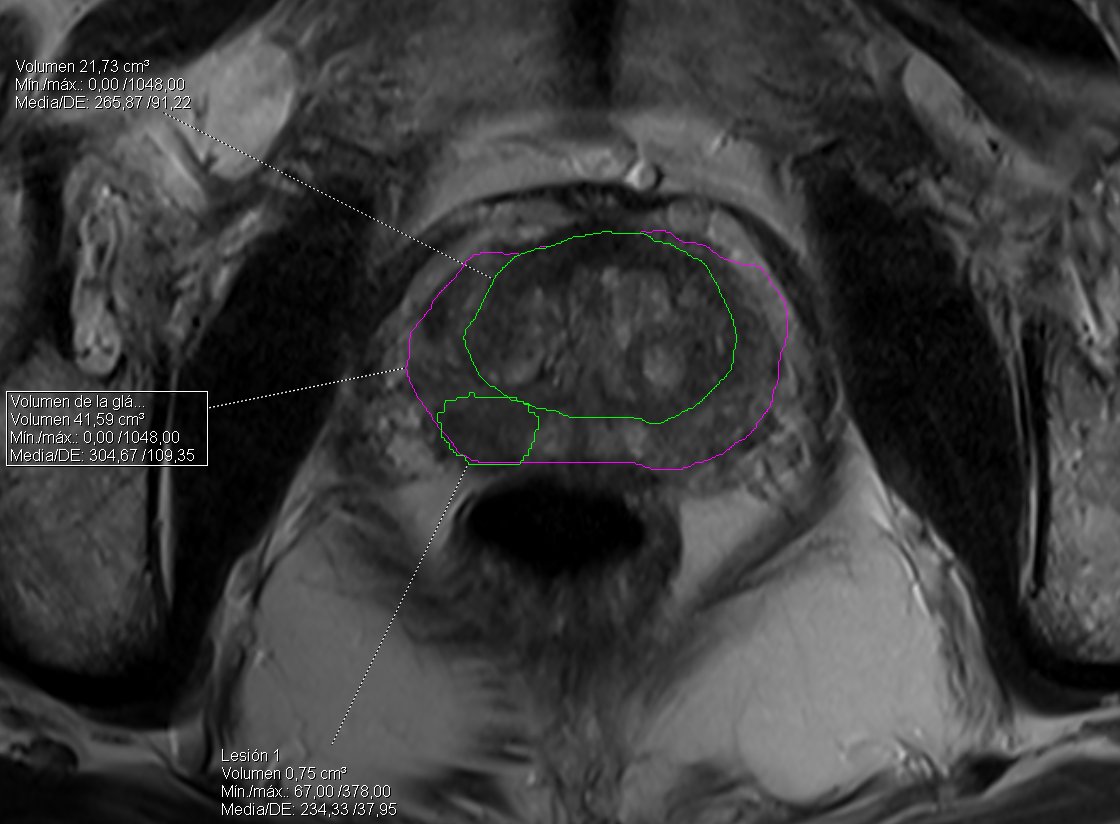

Starting to use the new prostate module in Singo.via. Very nice automatic segmentation and nodule detection @SiemensHealthES @alcazarandres85 @DiegoPereira_Rx @VictorSuarez_Rx